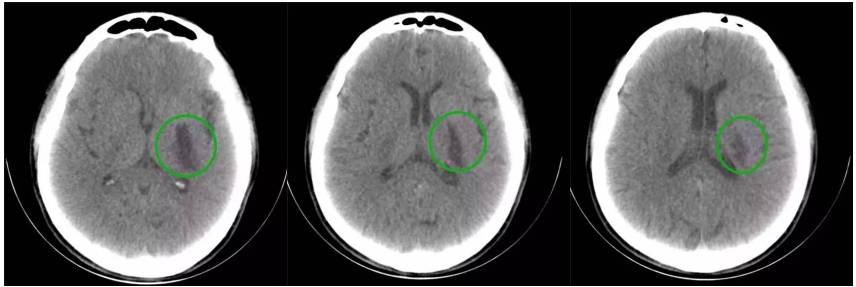

16层移动CT脑部扫描

16层移动CT脑部扫描(骨窗像)

急诊室脑梗塞移动CT床旁脑部扫描

脑科ICU脑出血移动CT床旁脑部扫描

脑科手术室脑损伤移动CT床旁脑部扫描